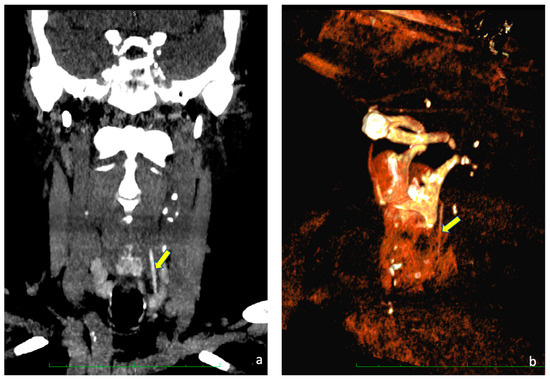

Figure 1.

(a) CT scan of the neck, coronal view. (b) 3D reconstruction. In both pictures, the yellow arrow points toward the toothpick.